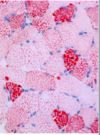

All three of these images are related to the same disease: what is that disease?

Dermatomyositis

Perifascicular atrophy with small muscle cells at teh edges of the fasicle with immune inflammatory accumulations

Key: small vessel damage is very important in this disease and can see that in the bottom picture